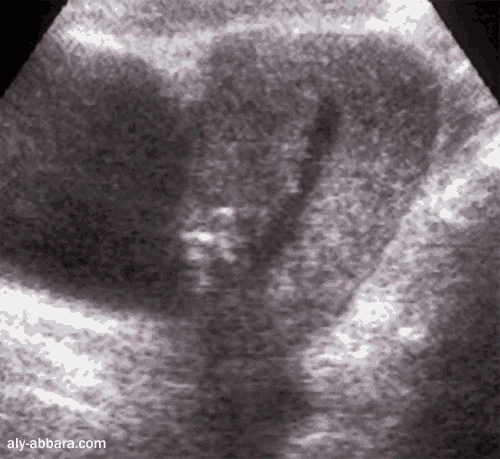

Aspect de l'utérus 14 jours après une césarienne avec

hystérotomie segmentaire transversale

On peut repérer la zone de la suture de l'utérus (l'hystérorrpahie)